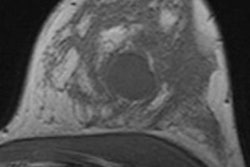

"The results of this study support the recommendation to use nonionizing radiation imaging techniques (such as MRI) as the main tool for surveillance in young BRCA1/2 mutation carriers," stated lead author Dr. Anouk Pijpe, PhD, a postdoctoral research fellow in the department of epidemiology and biostatistics at the Netherlands Cancer Institute. "While previous studies were based only on mammography or radiography, this large cohort study used estimates of an individual age-specific cumulative breast dose from various diagnostic radiation procedures as a measure of total diagnostic radiation exposure."